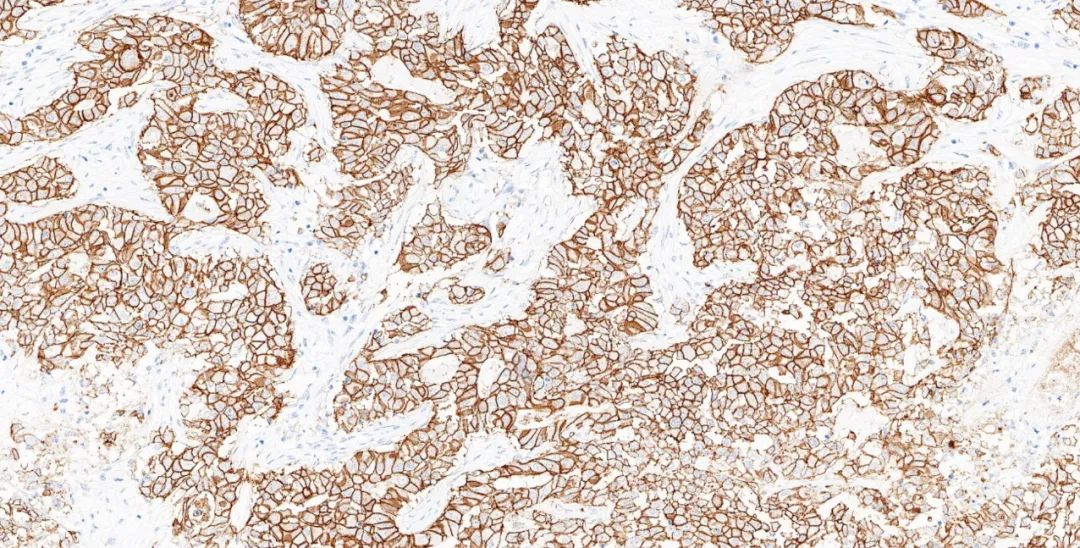

图4.基因科技免疫组化测评结果图:HER2(GT2245) 乳腺癌1-2+

图5.基因科技免疫组化测评结果图:HER2(GT2245) 乳腺癌3+